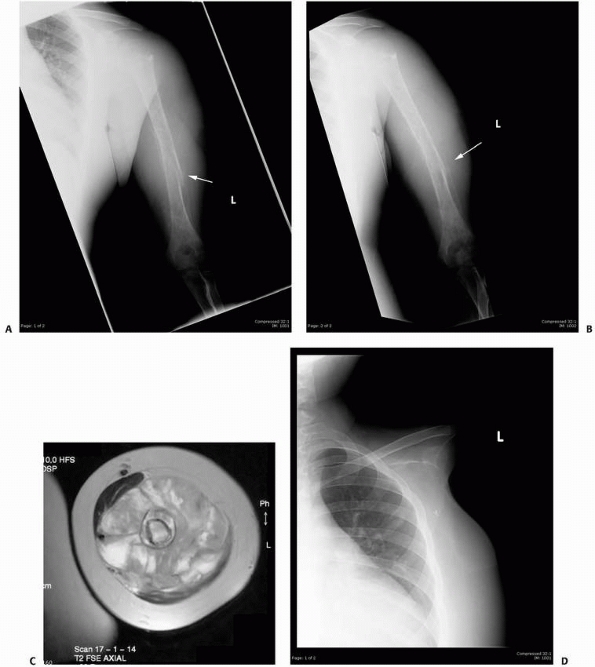

FIGURE 6-3 A 10-year-old boy presented with arm pain after low-energy trauma, 5 days prior. Anteroposterior (A) and lateral (B) radiographs of the right humerus show a nondisplaced pathologic fracture (A–arrow)

through a lytic lesion in the proximal humerus. The lesion is difficult to visualize and the periosteal reaction is also of concern (B–arrow). T2-weighted MRI images show a well-defined, fluid-filled cystic lesion, with fluid-fluid levels (D–arrow) and no soft tissue mass or other worrisome signs in the coronal (C) and axial (D) cuts. The diagnosis was consistent with unicameral bone cyst and conservative treatment was recommended. (Figures reproduced with permission from The Childrens Orthopaedic Center, Los Angeles, CA.) |